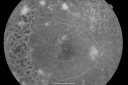

OD: Vertical C/D ratio is 0.1. There is extensive peripheral neovascularization. There is 2+ cystoid macular edema. There are patchy retinal hemorrhages and a moderately complete panretinal laser.

OS: Vertical C/D ratio is 0.1. There is 2+ cystoid macular edema. There is peripheral neovascularization and panretinal laser.

Photos confirm clinical findings.

FLUORESCEIN ANGIOGRAM: FA shows extensive active neovascularization in the mid periphery of each eye and leakage of fluorescein in the macula in the late frames of both eyes.

Proliferative Diabetic Retinopathy both eyes Type I Diabetic for 25 years632 views47-year-old woman with diabetes for 25 years and decreased vision for 3 months. OD 20/40, OS 20/40     (0 votes)